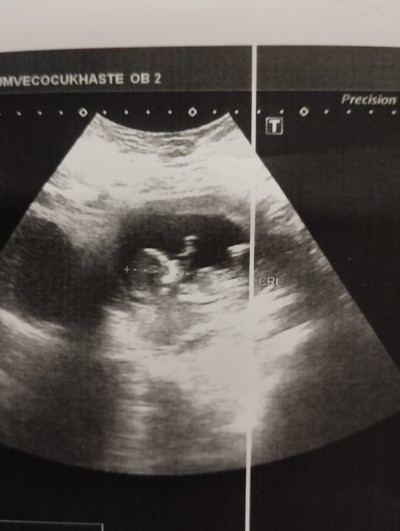

kızlar doktor bişi demedi sizce nedir cinsiyeti 12+2 haftalık

Gebelik haftası 12+2 haftalık

Erkeğe benzettim canım ben öyle hissettim kese yuvarlak hayırlısı olsun inşallah

Merhaba sağlıkla doğsun inşallah, bence 12 hafta bazen erken olabiliyor cinsiyet öğrenmek için, 13 haftadan sonra kesin belli olur diye biliyorum. <3

Bu bebiş erkek ☺️

buda ıkıncısı belkı daha nettır